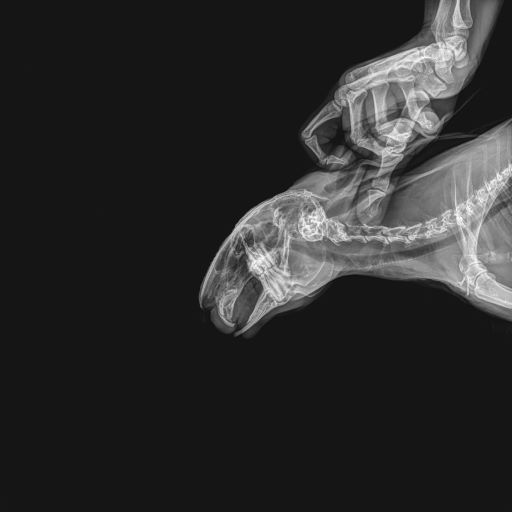

the vet MD of jpegs building @brokenbones91 3 years of computer science turned into degen veterinarian doctor 40k+ on tiktok only helping animals!